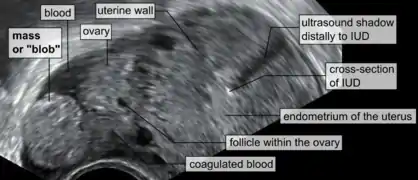

An ultrasound showing a gestational sac with fetal heart in the fallopian tube has a very high specificity of ectopic pregnancy. It involves a long, thin transducer, covered with the conducting gel and a plastic/latex sheath and inserted into the vagina.[32] Transvaginal ultrasonography has a sensitivity of at least 90% for ectopic pregnancy.[5] The diagnostic ultrasonographic finding in ectopic pregnancy is an adnexal mass that moves separately from the ovary. In around 60% of cases, it is an inhomogeneous or a noncystic adnexal mass sometimes known as the "blob sign". It is generally spherical, but a more tubular appearance may be seen in case of hematosalpinx. This sign has been estimated to have a sensitivity of 84% and specificity of 99% in diagnosing ectopic pregnancy.[5] In the study estimating these values, the blob sign had a positive predictive value of 96% and a negative predictive value of 95%.[5] The visualization of an empty extrauterine gestational sac is sometimes known as the "bagel sign", and is present in around 20% of cases.[5] In another 20% of cases, there is visualization of a gestational sac containing a yolk sac or an embryo.[5] Ectopic pregnancies where there is visualization of cardiac activity are sometimes termed "viable ectopic".[5]

Transvaginal ultrasonography of an ectopic pregnancy, showing the field of view in the following image A "blob sign", which consists of the ectopic pregnancy. The ovary is distinguished from it by having follicles, whereof one is visible in the field. This patient had an intrauterine device (IUD) with progestogen, whose cross-section is visible in the field, leaving an ultrasound shadow distally to it.

A "blob sign", which consists of the ectopic pregnancy. The ovary is distinguished from it by having follicles, whereof one is visible in the field. This patient had an intrauterine device (IUD) with progestogen, whose cross-section is visible in the field, leaving an ultrasound shadow distally to it. Ultrasound image showing an ectopic pregnancy where a gestational sac and fetus has been formed